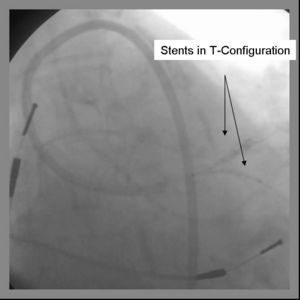

8) The parent stent is deployed across the side branch.

9) Angiography should now be performed to ensure adequate side branch coverage and stent deployment. The parent stent is deployed.

10) The side-branch is rewired. It is sometimes necessary to change wires to either a hydrophilic wire eg. Whisper, (Guidant, Temecula, California) or Pilot 50 or 150 (Guidant, Temecula, California), or Fielder (Abbott Vascular Devices, Redwood City, California), one of increasing stiffness eg. ASAHI Miracle Bros 3 (Abbott Vascular Devices, Redwood City, California), or both eg. Shinobi (Guidant, Temecula, California) or Confienza (Abbott Vascular Devices, Redwood City, California).